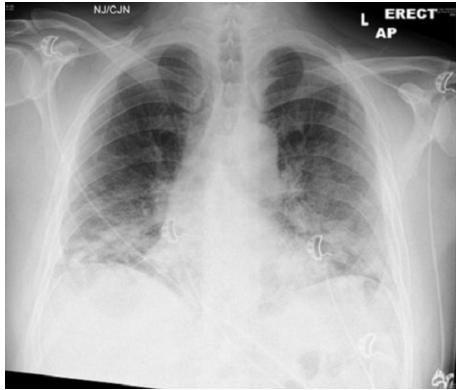

病例1::60岁男性,不吸烟,无其他疾病病史。感染新冠病毒后胸闷憋喘,遂至医院急诊就诊,测指氧饱和度为88%,动脉血气分析(FiO2 35%):pH 7.50,PaO2 51 mmHg,PaCO2 31.5 mmHg,HCO3- 26.6 mmol/L,BE 2.5 mmol/L,Lac 2.2 mmol/L。胸片示双下肺广泛磨玻璃影(图2)。入院1天后,患者氧合下降明显,需氧量增加,完善CT肺动脉造影(CTPA)检查未发现肺栓塞,广泛的磨玻璃改变及小叶间隔增厚(图3)。予地塞米松6 mg/d;病房清醒俯卧位,时间超过18 h/d,仰卧位时,患者反复出现低至82%的血氧饱和度,在不改变吸氧浓度情况下继续俯卧位,就能将其纠正至94%。患者最终好转出院,出院时血氧饱和度达到95%。病例2::35岁男性,轻度持续性哮喘、肥胖、阻塞性睡眠呼吸暂停(OSA)病史,因胸闷憋喘3 d入院,无发热、咽痛等不适。入院后因氧合不能维持行气管插管,同时予静脉糖皮质激素、利尿、扩张支气管治疗,7 d后顺利拔管。拔管后出现需氧量上升,但无其他感染征象及证据,氧合指数80 mmHg,吸氧浓度约80%。由于焦虑及不适,患者俯卧位仅能持续5 min,予阿普唑仑和俯卧位后,患者第2天可俯卧位2 h,俯卧位1 h时,吸氧量可将至40%,且在仰卧位后需氧量未再增加。